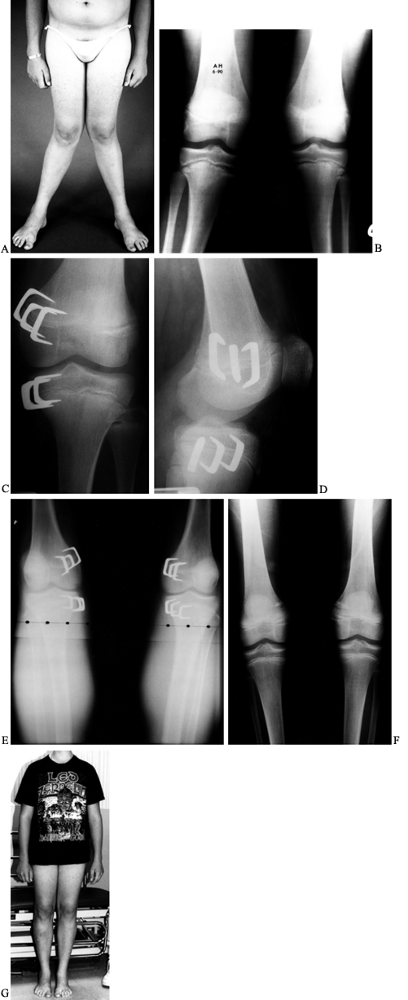

Figure 169.14. A: A 14-year-old boy with persistent severe physiologic genu valgum. B:

Standing AP radiograph of both lower extremities demonstrates a valgus deformity in the distal femora and proximal tibiae. Observe the physeal widening at the proximal tibial physes. A metabolic evaluation was normal. C: Postoperative radiograph of the left knee after stapling of the medial aspect of the distal femoral and proximal tibial epiphyses shows the three staples used to bracket each epiphysis. D: Lateral radiograph. E: Standing radiograph of both knees 9 months postoperatively shows excellent correction of the genu valgum deformities. F: On a standing radiograph 6 months after staple removal, physiologic alignment is being maintained. G: Clinical photograph. |